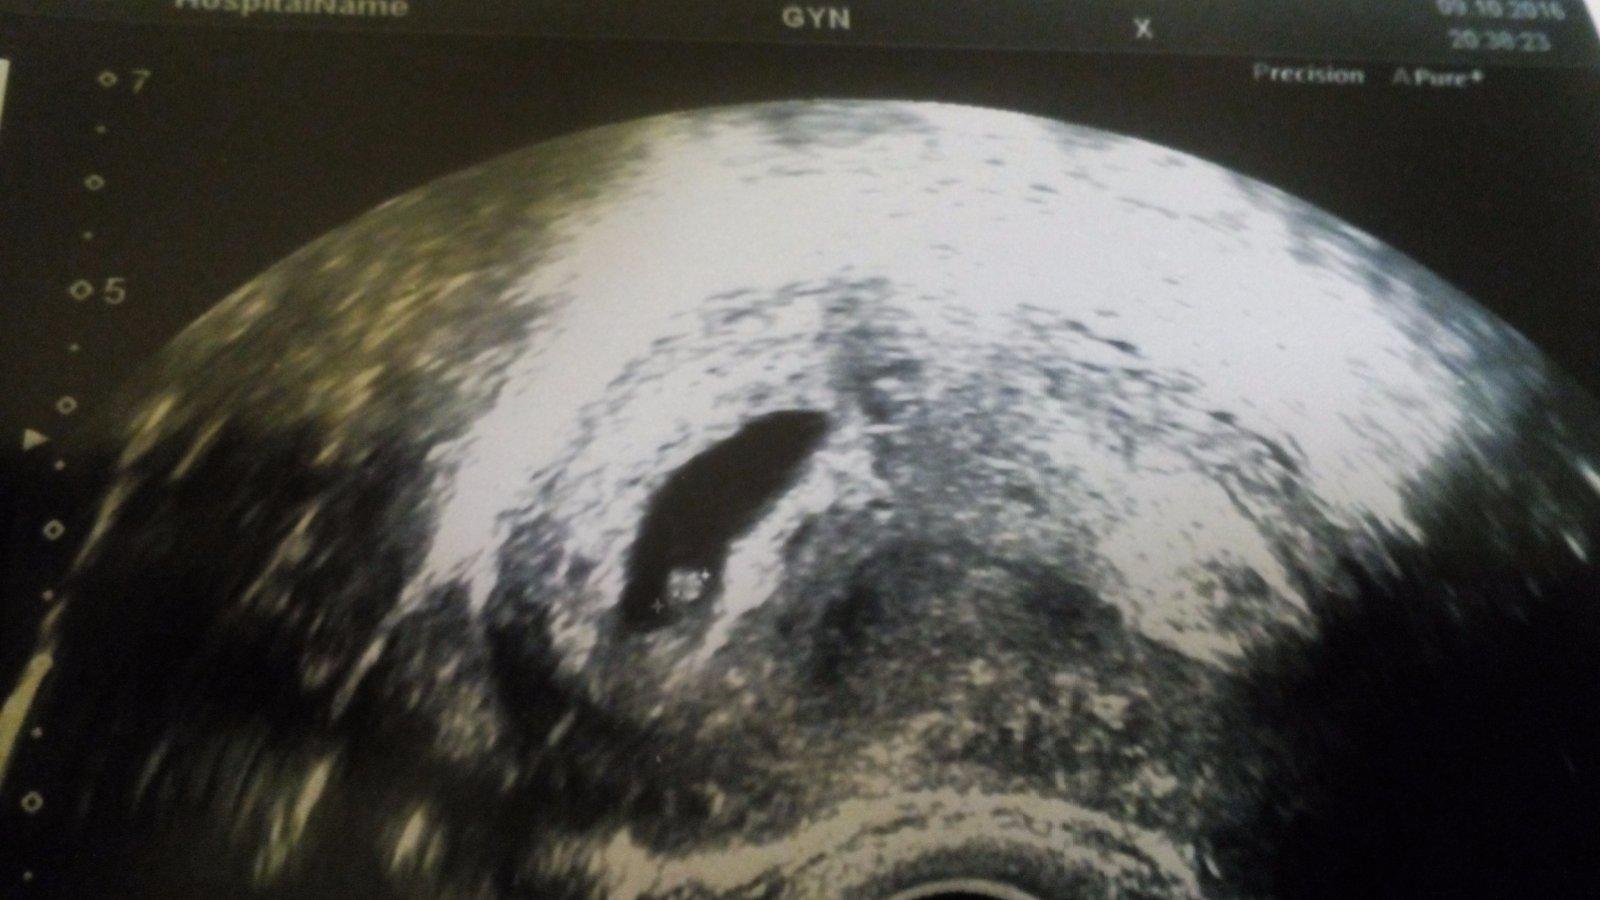

@ssaskiaa ahojky ja mela v 6+2tt videt tohle 🙂 Brouček byl malinky jako boruvka 🙂 a srdicko nam krasne blikalo 💕😍👶